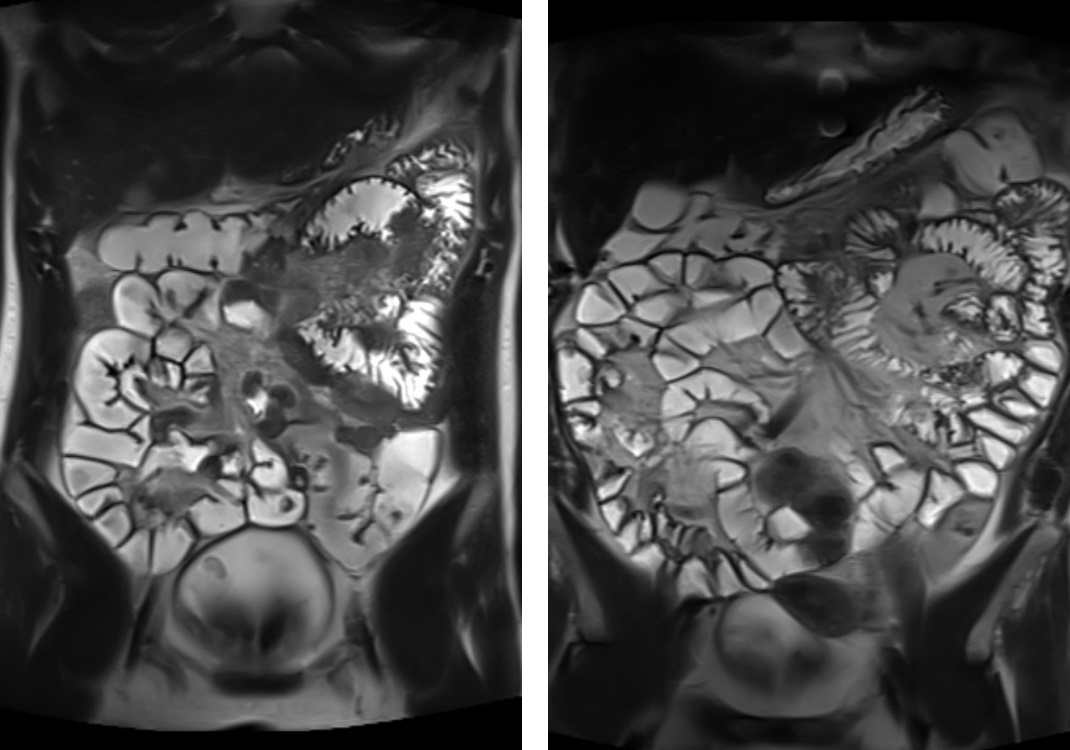

Die MR-Sellink ist eine spezielle kernspintomographische Untersuchung des Dünndarms. Sie dient vorwiegend zur Abklärung entzündlicher oder tumoröser Veränderungen des Dünndarms. Häufig wird diese Technik bei chronisch-entzündlichen Darmerkrankungen wie Morbus Crohn oder Colitis ulcerosa eingesetzt.